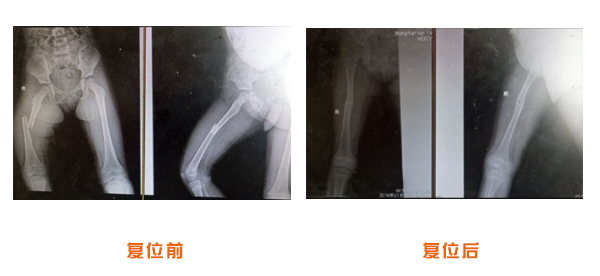

肥城市安駕莊梁氏骨科醫(yī)院是一所以梁氏手法正骨配合膏藥為特色的現(xiàn)代化專科醫(yī)院。

梁氏骨科術(shù)始創(chuàng)于清雍正年間,歷經(jīng)八代,至今已有三百年歷史。據(jù)1929年泰安縣志載“梁瑞圖先生,字增生,號蓮峰,安駕莊人,精岐黃并發(fā)明接骨,凡跌打車凡跌打車軋皮不破而碎骨者......【詳細(xì)】 |